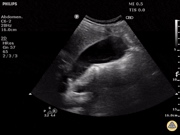

SONO 252 -CHOLELITHIASIS